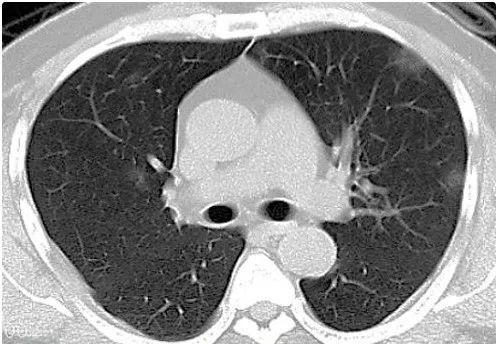

摘要:根据最新数据,新型冠性肺炎疫情仍在全球范围内持续。科技在疫情防控中发挥着重要作用,为守护新生活提供了有力支持。需要继续关注疫情动态,加强防控措施,共同应对这一全球挑战。

随着全球科技的飞速发展,我们正面临着前所未有的挑战——新型冠性肺炎,在这个关键时刻,一款全新的高科技产品应运而生,以卓越的性能和前沿的技术,为我们带来了全新的防控体验,本文将为您详细介绍这款产品的最新数据、功能亮点、使用体验,以及它如何改变生活并激发科技爱好者的无限兴趣。

截至最新报告,全球新型冠性肺炎感染人数仍在不断攀升,随着这款高科技产品的广泛应用,我们对疫情的防控工作取得了显著成效,该产品凭借其强大的功能亮点和使用体验,为防控工作提供了强有力的支持。